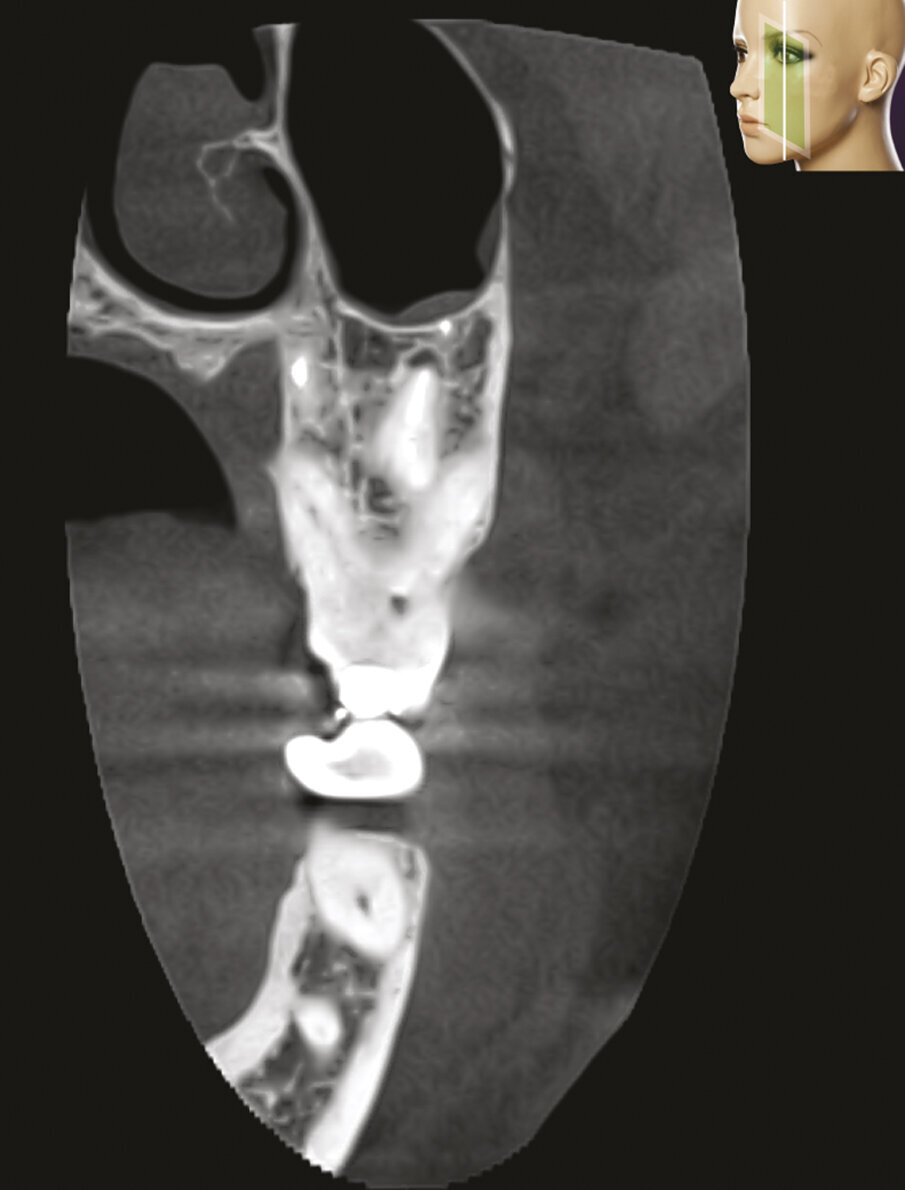

L’interpretazione di un’immagine bidimensionale può dare informazioni errate per una serie di fattori comprendenti la zona anatomica esaminata, la sovrapposizione di strutture vicine sia dentali che dento-alveolari circostanti8. A causa delle sovrapposizioni, le radiografie periapicali mostrano solo aspetti limitati, dovuti ad una visione bi-dimensionale della vera anatomia tri-dimensionale (Figg. 1a-2e)9, 10. Inoltre nelle radiografie tradizionali si hanno spesso delle distorsioni geometriche delle strutture anatomiche esaminate11. Tutti questi problemi possono essere superati utilizzando immagini ottenute con volumi piccoli o comunque limitati di Cone Beam Computed Tomography, che fornisce immagini accurate tri-dimensionali dei denti e delle strutture dento-alveolari circostanti9-11.

La CBCT è ottenuta utilizzando una piattaforma rotante alla quale sono fissati una sorgente radiogena e un rivelatore. Una sorgente di radiazioni ionizzanti di forma conica viene diretta attraverso il centro della zona interessata e la radiazione trasmessa ed attenuata viene proiettata entro una area del rivelatore dei raggi X situata al lato opposto. La sorgente radiogena e il rivelatore ruotano attorno ad un fulcro fisso situato all’interno della regione interessata. Durante la sequenza dell’esposizione, vengono acquisite centinaia di immagini di proiezioni piane della zona esaminata (FOV, Field Of View), in un arco di almeno 180°. Le immagini delle proiezioni vengono quindi integrate da un software per costruire una immagine volumetrica. Con questa singola rotazione, la CBCT fornisce immagini tridimensionali precise, immediate e accurate8. Le risultanti informazioni vengono digitalmente ricostruite ed interpretate fino a creare una interfaccia, dalla quale il clinico può interpretare nelle tre dimensioni le “sezioni” dei tessuti del paziente su molteplici piani: assiale, sagittale e coronale (Fig. 4). Al giorno d’oggi la CBCT è considerata una metodica complementare per applicazioni specifiche ma non in sostituzioni delle radiografie bi-dimensionali12.

Figg. 4a-4c - - La CBCT offre la possibilità di fornire e immagazzinare immagini radiografiche leggibili su vari piani sia orizzontali che verticali: assiale, sagittale e coronale.

Figg. 4a-4c - La CBCT offre la possibilità di fornire e immagazzinare immagini radiografiche leggibili su vari piani sia orizzontali che verticali: assiale, sagittale e coronale.